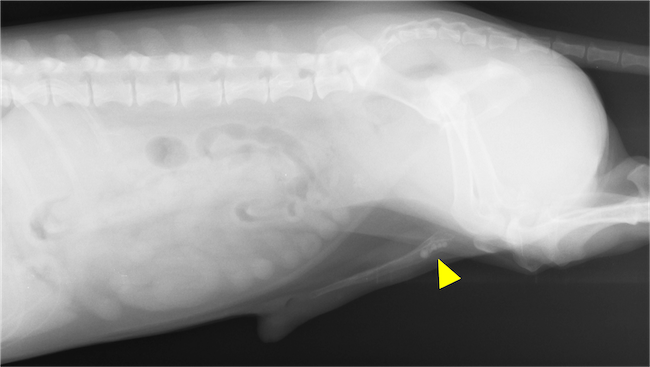

排尿できずに拡張した膀胱

膀胱アトニーとは膀胱の収縮力が失われ、完全な排尿ができずに膀胱内に尿が残ってしまう病気です。

症状としては排尿時の痛み、尿が出ない、尿漏れ、尿の過剰な蓄積による腹部の膨大などがあります。